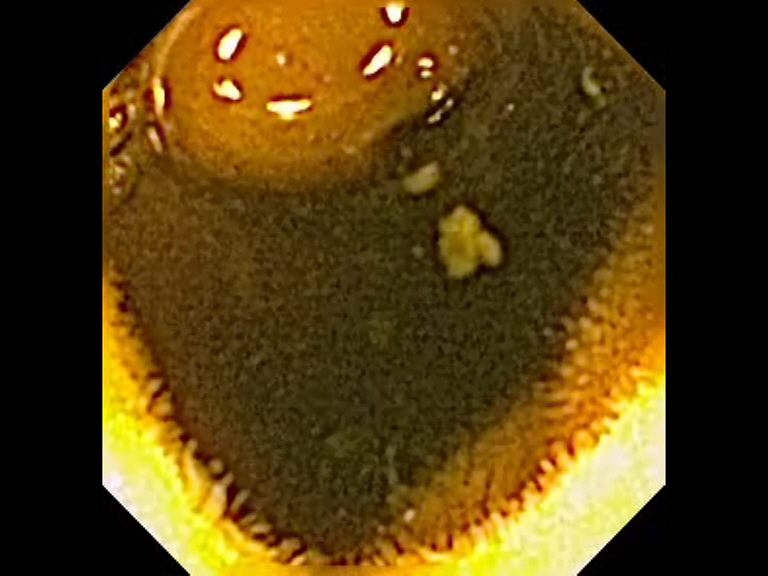

Se presenta el caso de una paciente de 85 años con anemia ferropénica y SOH + con gastroscopia y colonoscopia normales, apreciando en el estudio con cápsula endoscópica una lesión tumoral en íleon proximal probablemente de unos 3 cm, con ulceración en el vértice. Aunque no de forma concluyente, el aspecto endoscópico nos orienta a un tumor GIST ileal. Este hallazgo se confirmó en la pieza quirúrgica.